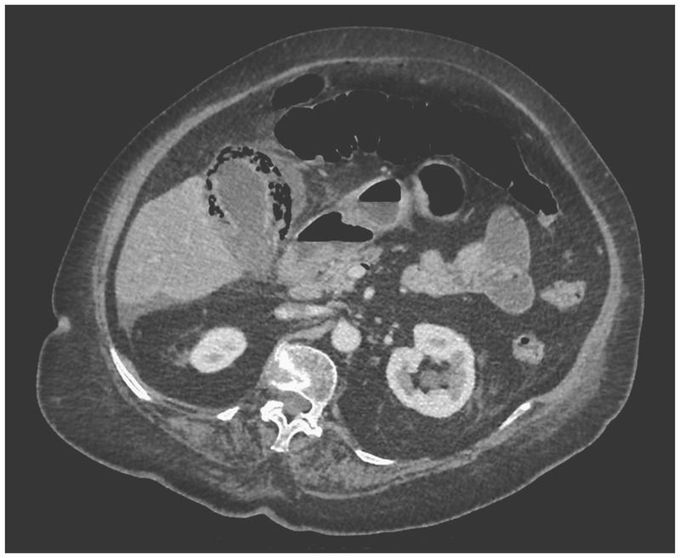

An 80-year-old man with a history of hypertension presented to the emergency department with a 2-day history of abdominal pain in the right upper quadrant. The patient was febrile. On physical examination, he had abdominal tenderness in the right upper quadrant, and Murphy’s sign was positive. Laboratory studies revealed a white-cell count of 20,000 per cubic millimeter (reference range, 4000 to 10,000). The alanine aminotransferase, aspartate aminotransferase, bilirubin, and lipase levels were normal. Findings on computed tomography of the abdomen included the presence of air encircling an inflamed gallbladder, with air tracking along the wall of the superior mesenteric vein, and a diagnosis of emphysematous cholecystitis was made. Intravenous broad-spectrum antibiotic agents were initiated, and a laparoscopic cholecystectomy was performed. A gangrenous and perforated gallbladder, including two gallstones, was resected. Bile cultures grew Escherichia coli and Klebsiella pneumoniae. The patient recovered after the surgery and was treated with a 10-day course of antibiotics. At a follow-up visit 4 weeks after discharge from the hospital, he was doing well and reported no abdominal pain.